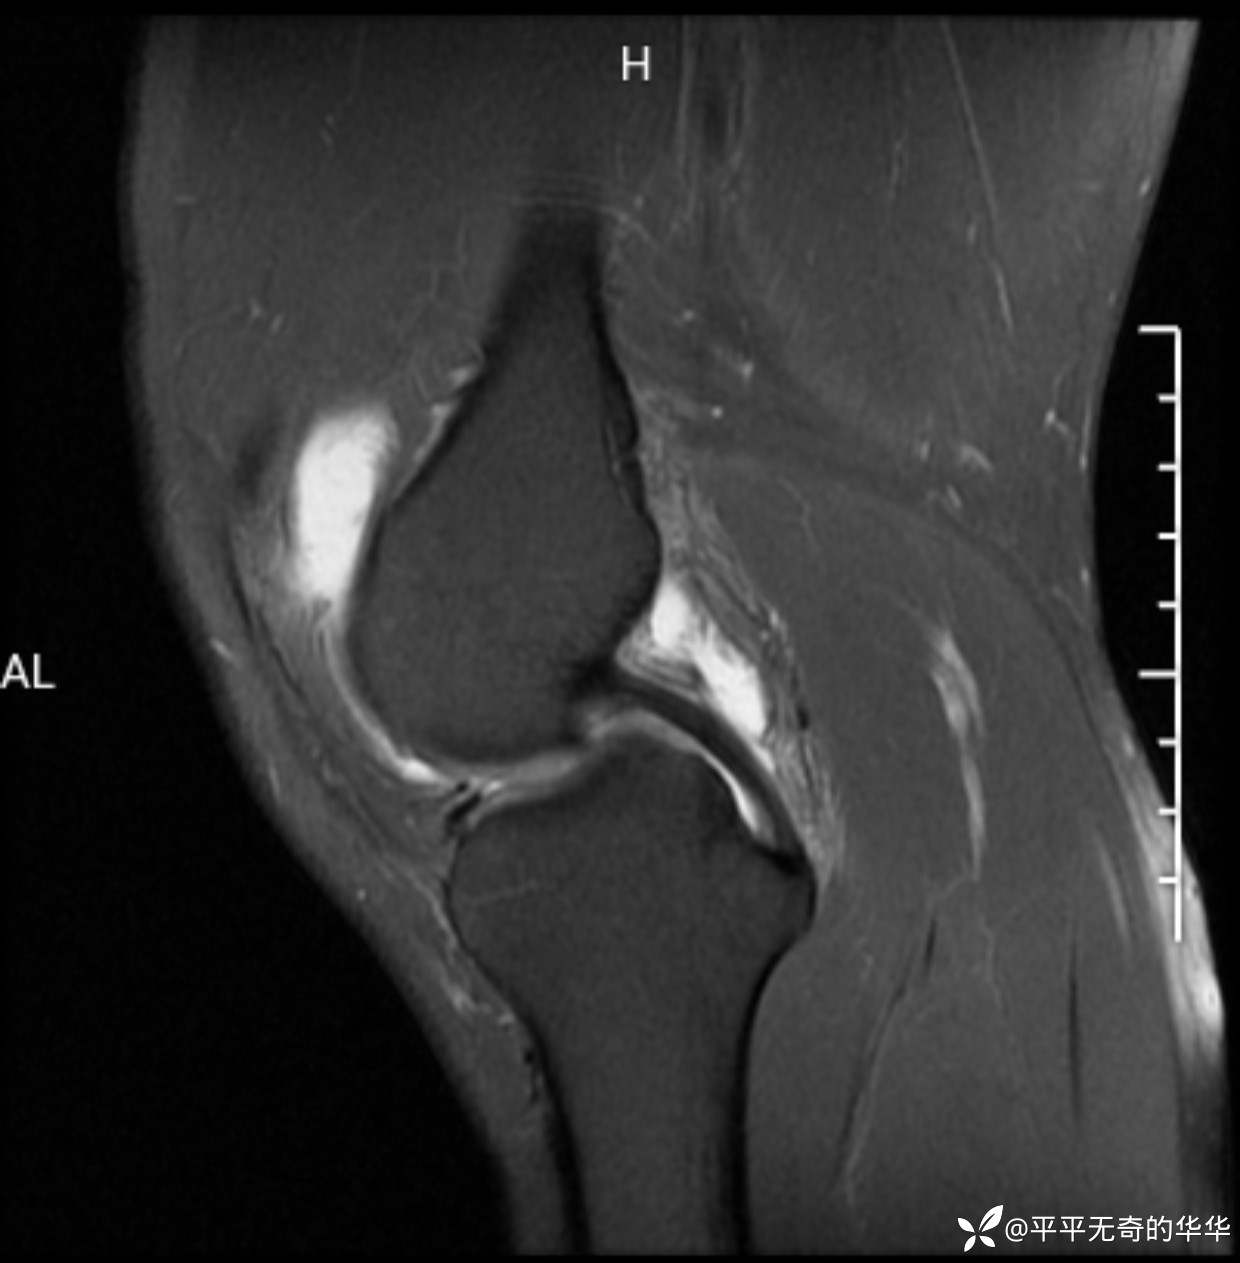

辅助检查:膝关节平片未见异常。磁共振影像如下。